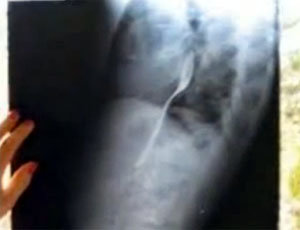

병원에서 촬영한 엑스레이 사진을 보면 알 수 있듯이, 칼린체스쿠가 병원을 찾았을 당시 포크는 칼린체스쿠의 목에 걸려 있었다.

의사들은 문제의 포크가 현재 칼린체스쿠의 식도에 걸려 있는 상태이며 포크가 소화 기관쪽으로 내려온 뒤 수술을 하는 것이 더 안전하다고 판단해 일단 칼린체스쿠를 집으로 돌려보냈다. 포크가 기도를 막고 있거나 생명 유지와 관련된 중요 기관을 막고 있지 않기 때문에 가능한 결정이었다. 의사들은 칼린체스쿠에게 ‘자연스러운 과정’을 통해 포크가 몸에서 빠져나가길 기다려보자고 제안했다.